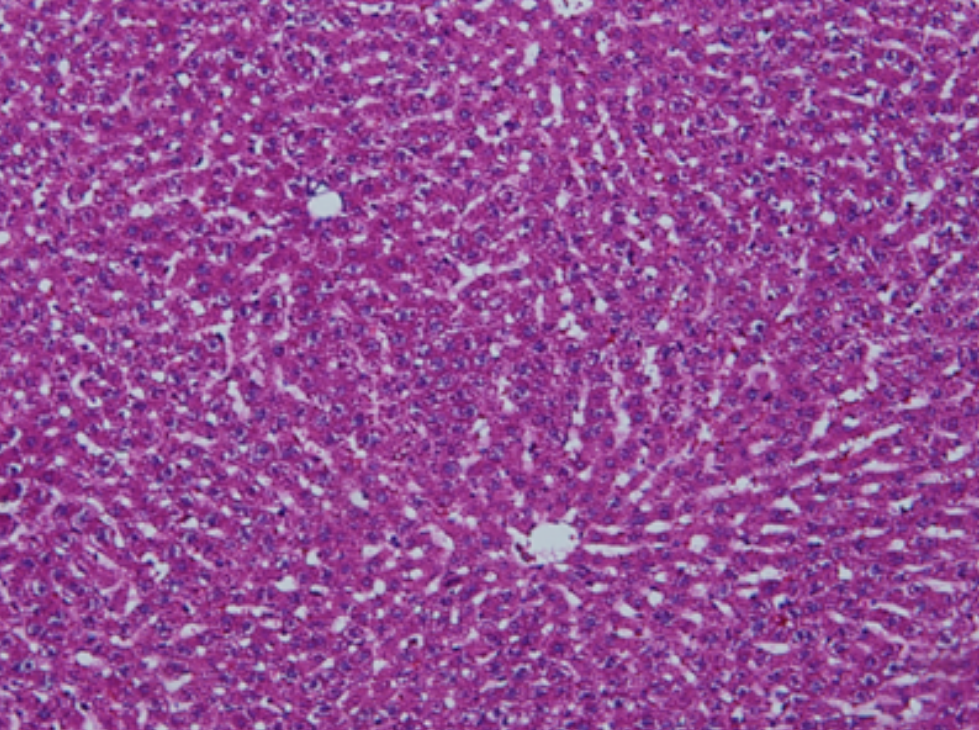

HE染色,全称苏木精-伊红染色法(Hematoxylin and Eosin staining),是最常见的组织切片染色技术之一,用于在显微镜下观察和分析组织或细胞的结构和形态。

虽然HE染色是最常见且最基础的染色技术之一,😭但在实验过程中,很容易出现各种情况导致染色切片质量参差不齐。所以,小编根据以往实验经验,给大家整理归纳出了15个HE染色中的常见问题,还包含问题原因分析以及解决方法哦~